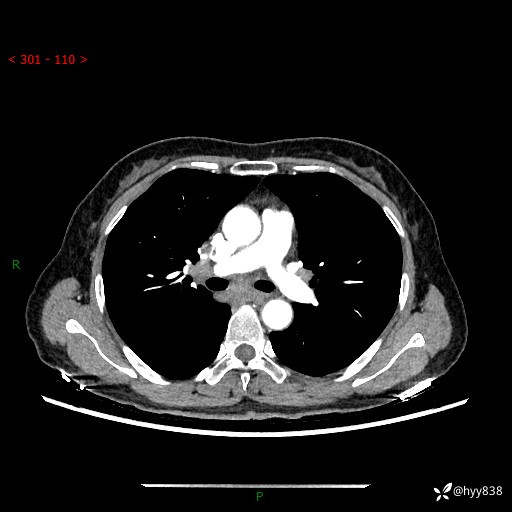

【患者信息】:58岁/女

【主诉】:体检发现肺结节

【检查】:胸部CT平扫+增强